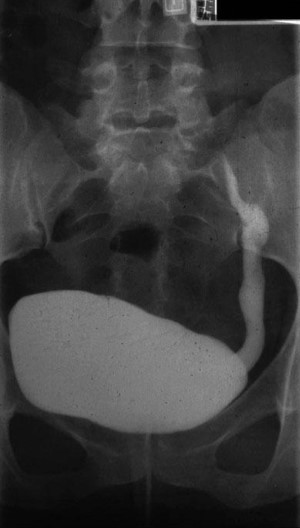

Urinary system anatomy:

Interpretation of common urinalysis results:

Common X-ray Findings: